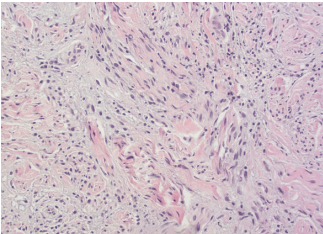

A punch biopsy revealed pleomorphic spindle cells infiltrating the deep dermis, positive for S100, vimentin, and SOX10, and negative for epithelial markers and other controls (Figure 2 and Figure 3). A second biopsy was S100 and SOX10 positive and Melanin-A and HMB45 negative (Figure 3). The case was subsequently sent to the Joint Pathology Center, which confirmed spindle cell proliferation and suspicion for desmoplastic melanoma. An 18F-FDG positron emission tomography-computed tomography scan showed a subcutaneous mass (6.7 x 2.5 cm) in the left mid-abdominal wall. The case was discussed at the Melanoma/Skin Cancer Tumor Board Conference, and the family opted for palliation, agreeing to a wide local excision with possible skin graft but declining sentinel lymph node dissection.